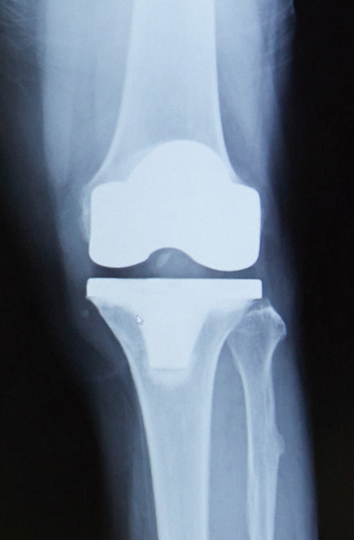

人工関節部分置換術後のレントゲン 人工膝関節全置換術後のレントゲン

人工関節部分置換術後(左)、人工膝関節全置換術後(右)のレントゲン

人工膝関節置換術には、全置換術と部分置換術があります。傷んでいる部分が膝の内側のみの場合は、部分的に取り換えればよいわけです。部分置換術では、傷んでいない軟骨や靭帯が温存され、手術による体への侵襲も全置換術よりも小さくてすみます。術後の筋力や関節の動きの改善が早く、早期の退院が可能です。さらに、全置換術に比べて部分置換術では、靭帯など残る部分が多いため、自分の膝としてつかいこなしやすいと感じる方は少なくないようです。一方、軟骨などの変形が膝関節の内側、外側など膝関節全体にまで及んでいる場合や、骨粗鬆症によって骨が非常にもろくなっている場合などは全置換術の適応となります。全置換術では膝関節をそっくり人工物に入れ替えるので、しっかりとした矯正ができ、安定した膝になることが期待できます。